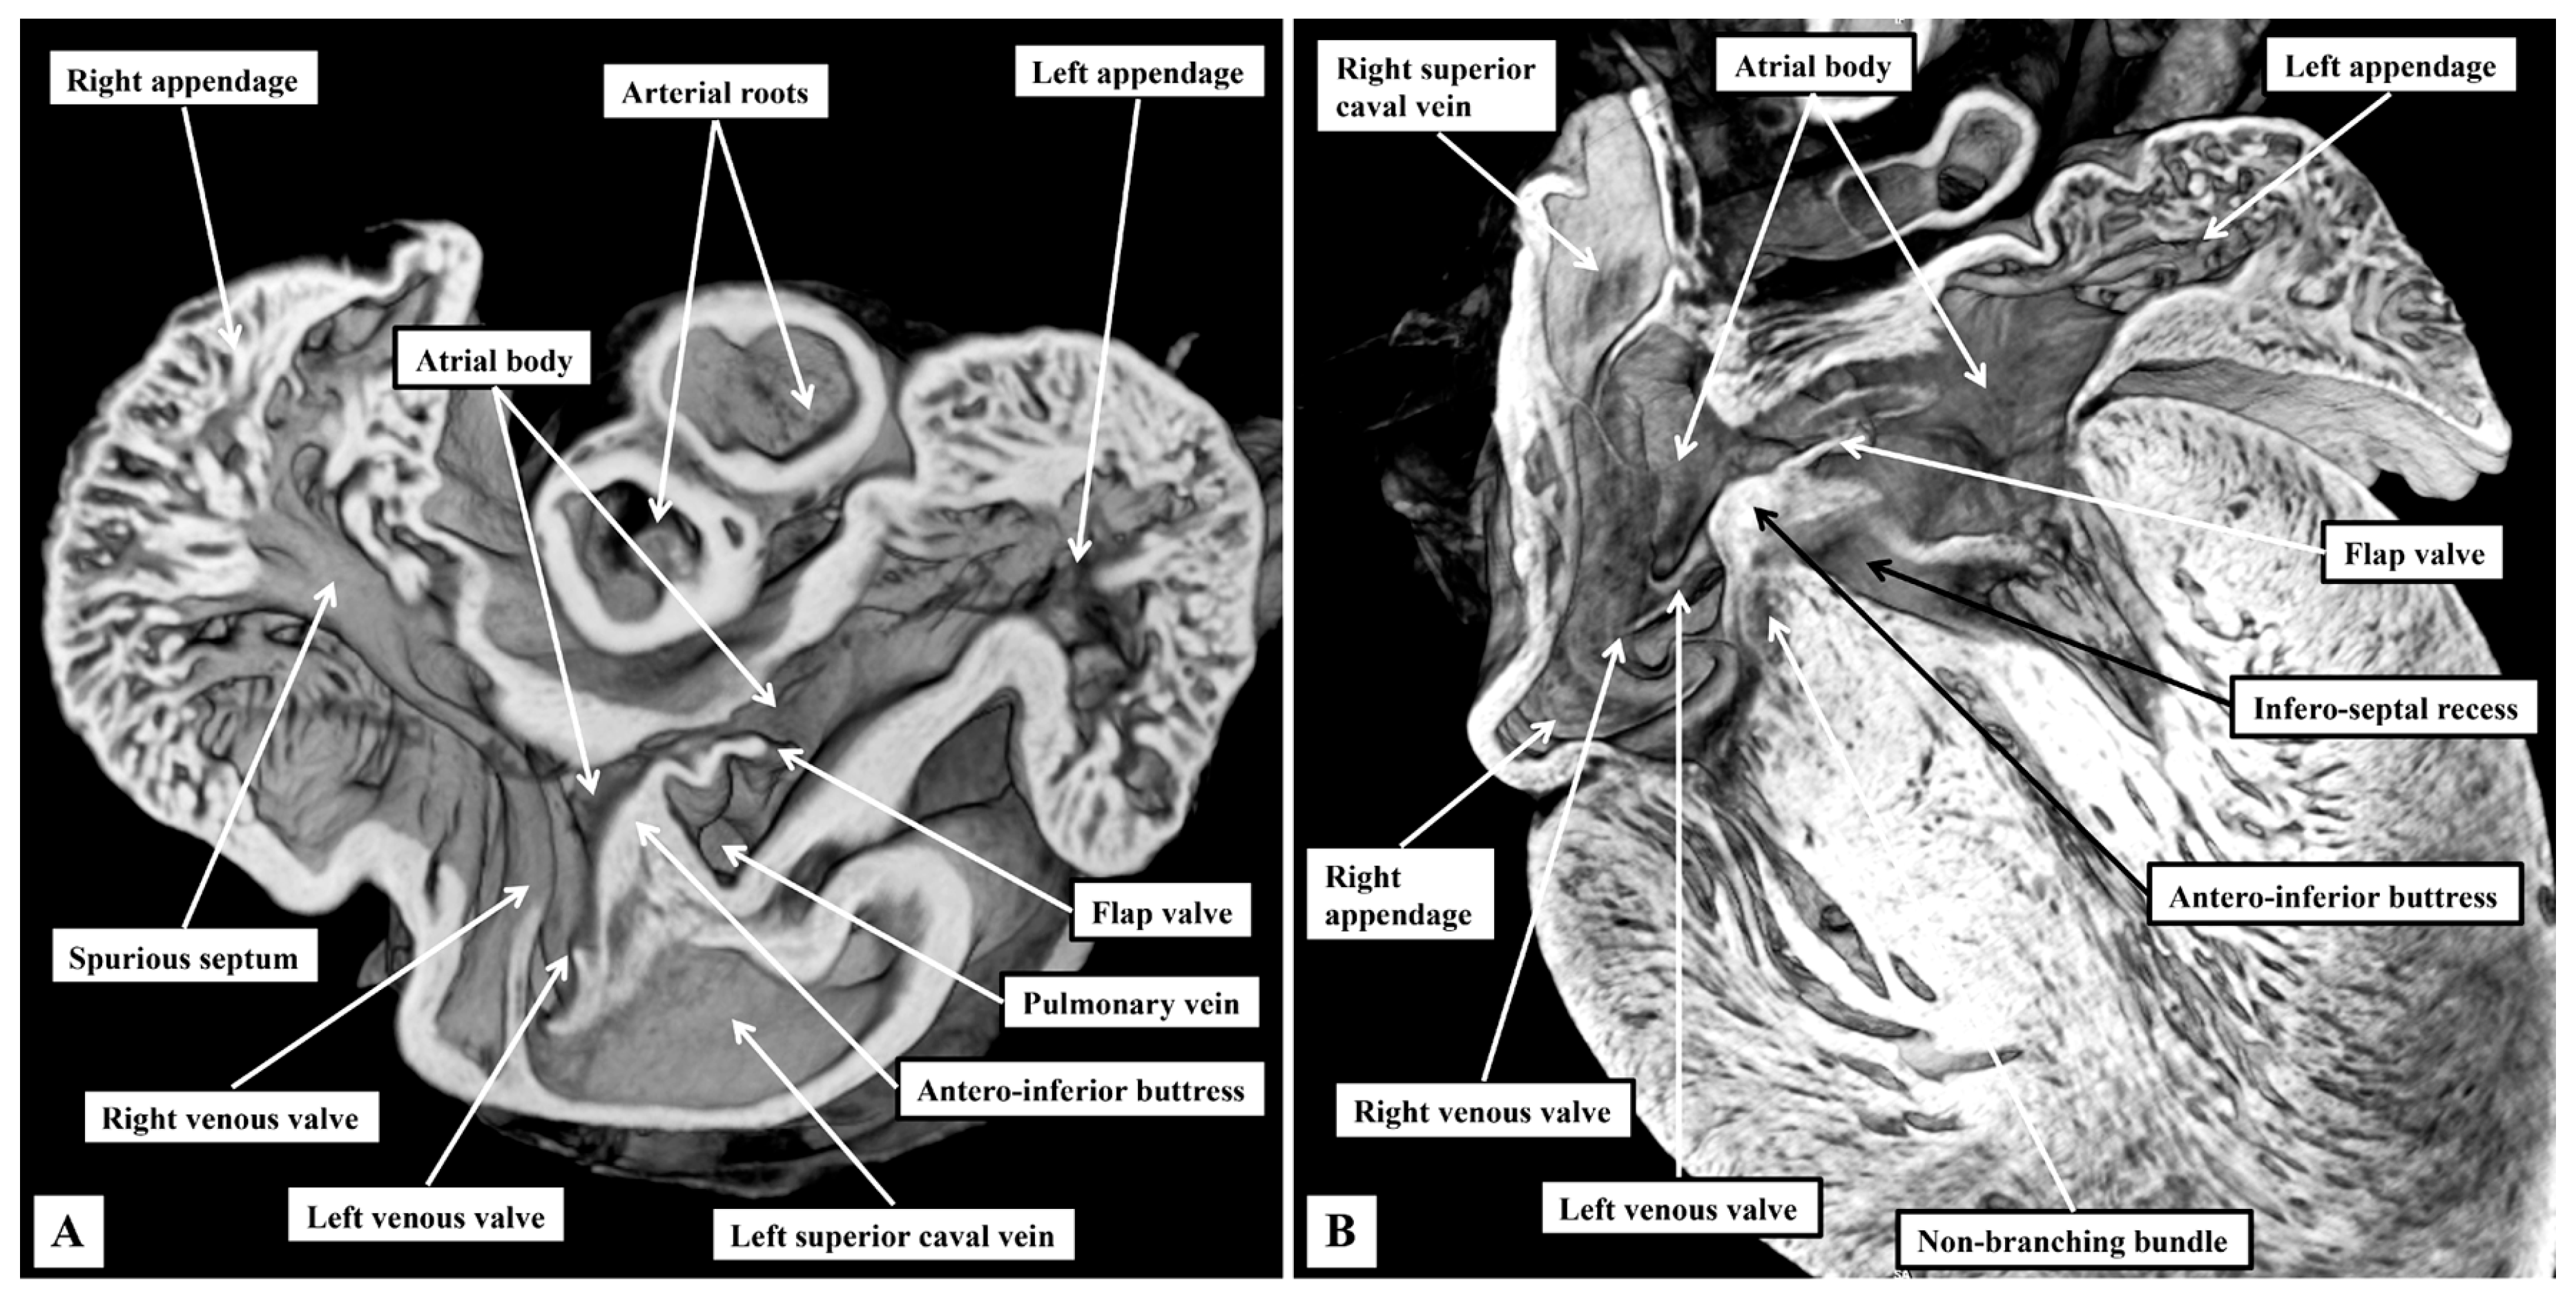

3.1. Gross Anatomy